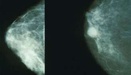

Кому нужно генетическое тестирование на рак молочной железы?

Поставщики медицинских услуг должны понимать важность раннего скрининга и достижений в области генетики рака, что позволяет сохранить жизни.